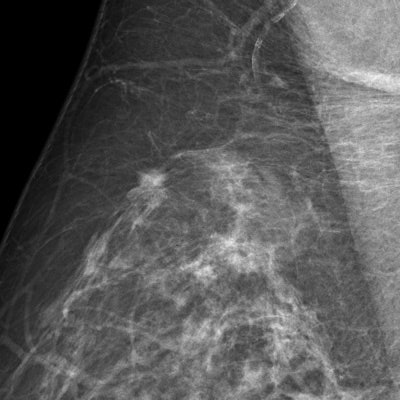

"Traditional CAD doesn't take into account risk factors such as age or genetics. This combined with its 98% sensitivity for finding microcalcifications means that the radiologist must decide whether or not the often numerous findings are clinically relevant," said Bick, who presented an update on breast CAD at today's session.

![A 68-year-old asymptomatic woman underwent routine mammographic screening (above). A subtle small spiculated mass was correctly detected by CAD in the upper-outer quadrant of the right breast, best seen on the mediolateral oblique (MLO) view (below). Percutaneous biopsy and subsequent surgical excision confirmed a 10-mm well-differentiated, lymph-node-negative invasive ductal cancer in the right breast [pT1b pN0 (sn) G1], which had an excellent prognosis due to its early detection through mammography screening. Images courtesy of Dr. Ulrich Bick.](https://img.auntminnieeurope.com/files/base/smg/all/image/2015/03/ame.2015_03_06_00_09_16_89_2015_03_06_CAD3.png?auto=format%2Ccompress&fit=max&q=70&w=400)

Results from the European breast cancer diagnosis project, HAMAM, which uses CAD in a more patient-tailored approach, are promising. The project integrates MRI, mammography, and ultrasound with risk factors such as age and gene mutation carrier information. Some risk factors, such as breast density and composition, can even be extracted and factored into CAD's findings.

"For example, CAD could distinguish that four calcifications clustered together in a young patient with dense breasts are more likely to be relevant than in a 70-year-old with low-density fatty breasts," Bick noted. "At present the commercial application of CAD is in pure detection. However, the research points to integrating different modalities, risk factors, and detection into a clinical decision aid."

For the moment, some of CAD's advantages are clear-cut: e.g., finding microcalcifications is tedious for the reader, as the image needs to be checked in quadrants due to resolution issues. CAD, however, speeds up the process by looking at the full image in full resolution and pointing to these microcalcifications. This frees up the human reader to concentrate on other areas such as density, masses and architectural distortions for which the computer is less trained. However, with CAD's average of one false prompt per case, time still risks being wasted on recalls, which in a screening program should not exceed 5% for a human reader.